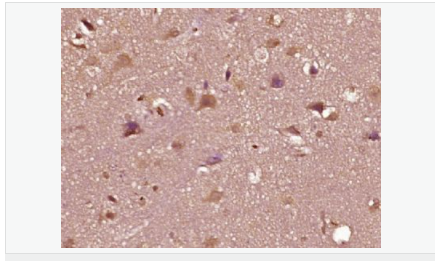

| 產(chǎn)品應用 | WB=1:500-2000 ELISA=1:5000-10000 IHC-P=1:100-500 IHC-F=1:100-500 Flow-Cyt=1ug/Test IF=1:100-500 (石蠟切片需做抗原修復) not yet tested in other applications. optimal dilutions/concentrations should be determined by the end user. |

| 產(chǎn)品介紹 | The androgen receptor gene is more than 90 kb long and codes for a protein that has 3 major functional domains: the N-terminal domain, DNA-binding domain, and androgen-binding domain. The protein functions as a steroid-hormone activated transcription factor. Upon binding the hormone ligand, the receptor dissociates from accessory proteins, translocates into the nucleus, dimerizes, and then stimulates transcription of androgen responsive genes. This gene contains 2 polymorphic trinucleotide repeat segments that encode polyglutamine and polyglycine tracts in the N-terminal transactivation domain of its protein. Expansion of the polyglutamine tract causes spinal bulbar muscular atrophy (Kennedy disease). Mutations in this gene are also associated with complete androgen insensitivity (CAIS). Two alternatively spliced variants encoding distinct isoforms have been described. [provided by RefSeq, Jul 2008] Function: Steroid hormone receptors are ligand-activated transcription factors that regulate eukaryotic gene expression and affect cellular proliferation and differentiation in target tissues. Transcription factor activity is modulated by bound coactivator and corepressor proteins. Transcription activation is down-regulated by NR0B2. Activated, but not phosphorylated, by HIPK3 and ZIPK/DAPK3. [ENZYME REGULATION] AIM-100 (4-amino-5,6-biaryl-furo[2,3-d]pyrimidine) suppresses TNK2-mediated phosphorylation at Tyr-267. Inhibits the binding of the Tyr-267 phosphorylated form to androgen-responsive enhancers (AREs) and its transcriptional activity. Subunit: Binds DNA as a homodimer. Part of a ternary complex containing AR, EFCAB6/DJBP and PARK7. Interacts with HIPK3 and NR0B2 in the presence of androgen. The ligand binding domain interacts with KAT7/HBO1 in the presence of dihydrotestosterone. Interacts with EFCAB6/DJBP, PELP1, PQBP1, RANBP9, RBAK, SPDEF, SRA1, TGFB1I1, ZNF318 and RREB1. Interacts with ZMIZ1/ZIMP10 and ZMIZ2/ZMIP7 which both enhance its transactivation activity. Interacts with SLC30A9 and RAD54L2/ARIP4. Interacts via the ligand-binding domain with LXXLL and FXXLF motifs from NCOA1, NCOA2, NCOA3, NCOA4 and MAGEA11. The AR N-terminal poly-Gln region binds Ran resulting in enhancement of AR-mediated transactivation. Ran-binding decreases as the poly-Gln length increases. Interacts with HIP1 (via coiled coil domain). Interacts (via ligand-binding domain) with TRIM68. Interacts with TNK2. Interacts with USP26. Interacts with RNF6. Interacts (regulated by RNF6 probably through polyubiquitination) with RNF14; regulates AR transcriptional activity. Interacts with PRMT2 and TRIM24. Interacts with GNB2L1/RACK1. Interacts with RANBP10; this interaction enhances dihydrotestosterone-induced AR transcriptional activity. Interacts with PRPF6 in a hormone-independent way; this interaction enhances dihydrotestosterone-induced AR transcriptional activity. Interacts with STK4/MST1. Interacts with ZIPK/DAPK3. Interacts with LPXN. Interacts with MAK. Part of a complex containing AR, MAK and NCOA3. Subcellular Location: Nucleus. Cytoplasm. Note=Predominantly cytoplasmic in unligated form but translocates to the nucleus upon ligand-binding. Can also translocate to the nucleus in unligated form in the presence of GNB2L1. Tissue Specificity: Isoform 2 is mainly expressed in heart and skeletal muscle. Post-translational modifications: Sumoylated on Lys-386 (major) and Lys-520. Ubiquitinated. Deubiquitinated by USP26. 'Lys-6' and 'Lys-27'-linked polyubiquitination by RNF6 modulates AR transcriptional activity and specificity. Phosphorylated in prostate cancer cells in response to several growth factors including EGF. Phosphorylation is induced by c-Src kinase (CSK). Tyr-534 is one of the major phosphorylation sites and an increase in phosphorylation and Src kinase activity is associated with prostate cancer progression. Phosphorylation by TNK2 enhances the DNA-binding and transcriptional activity and may be responsible for androgen-independent progression of prostate cancer. Phosphorylation at Ser-81 by CDK9 regulates AR promoter selectivity and cell growth. Phosphorylation by PAK6 leads to AR-mediated transcription inhibition. Palmitoylated by ZDHHC7 and ZDHHC21. Palmitoylation is required for plasma membrane targeting and for rapid intracellular signaling via ERK and AKT kinases and cAMP generation. DISEASE: Defects in AR are the cause of androgen insensitivity syndrome (AIS) [MIM:300068]; previously known as testicular feminization syndrome (TFM). AIS is an X-linked recessive form of pseudohermaphroditism due end-organ resistance to androgen. Affected males have female external genitalia, female breast development, blind vagina, absent uterus and female adnexa, and abdominal or inguinal testes, despite a normal 46,XY karyotype. Defects in AR are the cause of spinal and bulbar muscular atrophy X-linked type 1 (SMAX1) [MIM:313200]; also known as Kennedy disease. SMAX1 is an X-linked recessive form of spinal muscular atrophy. Spinal muscular atrophy refers to a group of neuromuscular disorders characterized by degeneration of the anterior horn cells of the spinal cord, leading to symmetrical muscle weakness and atrophy. SMAX1 occurs only in men. Age at onset is usually in the third to fifth decade of life, but earlier involvement has been reported. It is characterized by slowly progressive limb and bulbar muscle weakness with fasciculations, muscle atrophy, and gynecomastia. The disorder is clinically similar to classic forms of autosomal spinal muscular atrophy. Note=Caused by trinucleotide CAG repeat expansion. In SMAX1 patients the number of Gln ranges from 38 to 62. Longer expansions result in earlier onset and more severe clinical manifestations of the disease. Note=Defects in AR may play a role in metastatic prostate cancer. The mutated receptor stimulates prostate growth and metastases development despite of androgen ablation. This treatment can reduce primary and metastatic lesions probably by inducing apoptosis of tumor cells when they express the wild-type receptor. Defects in AR are the cause of androgen insensitivity syndrome partial (PAIS) [MIM:312300]; also known as Reifenstein syndrome. PAIS is characterized by hypospadias, hypogonadism, gynecomastia, genital ambiguity, normal XY karyotype, and a pedigree pattern consistent with X-linked recessive inheritance. Some patients present azoospermia or severe oligospermia without other clinical manifestations. Similarity: Belongs to the nuclear hormone receptor family. NR3 subfamily. Contains 1 nuclear receptor DNA-binding domain. SWISS: P10275 Gene ID: 367 Database links: Entrez Gene: 367 Human Entrez Gene: 11835 Mouse Omim: 313700 Human SwissProt: P10275 Human SwissProt: P19091 Mouse Unigene: 496240 Human Unigene: 39005 Mouse Unigene: 394224 Mouse Unigene: 439657 Mouse Unigene: 9813 Rat Important Note: This product as supplied is intended for research use only, not for use in human, therapeutic or diagnostic applications. AR是一個由917個氨基酸組成的蛋白質(zhì),位于雄激素靶組織細胞中或細胞表面上的特異分子部位或結(jié)構(gòu)。 AR在前列腺癌中起著重要的作用,研究表明AR的表達與組織分型形成一定的相關(guān)性 ,AR在高分化的腫瘤中表達較多,而在低分化的腫瘤中表達較少。用于前列腺癌的檢測,指導臨床治療,目前可用于乳腺癌、食道癌等各項腫瘤的研究。 |